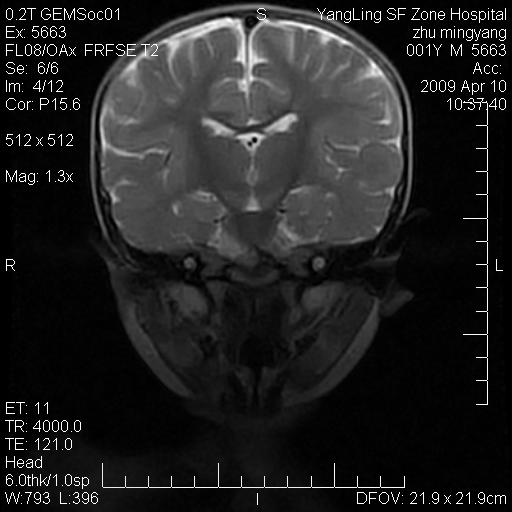

患者:1岁半,两天前外伤收住我院,ct检查小脑占位

考虑星形细胞瘤,建议增强

髓母细胞瘤或血管母细胞瘤,增强后可以鉴别;影像资料见 <。鱼博浪老师的《中枢神经系统ct与mr鉴别诊断》 小脑部肿瘤章节。

髓母细胞瘤或血管母细胞瘤!支持!

支持考虑髓母细胞瘤

考虑----髓母细胞瘤可能性大

考虑髓母细胞瘤或室管膜瘤。

支持髓母细胞瘤。

考虑髓母细胞瘤。

考虑髓母细胞瘤或星形细胞瘤

考虑髓母细胞瘤.

考虑髓母细胞瘤可能性大。

小脑肿瘤.考虑髓母细胞瘤可能.

就病灶部位及临床资料首先考虑髓母.